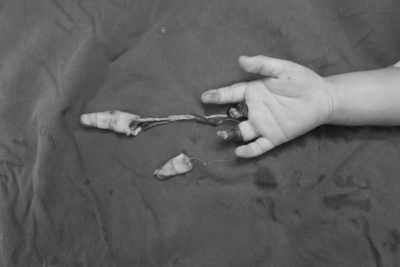

断指再植案例

2岁宝宝右手的中指被机器挤压撕脱离断,环指末节脱套指骨外漏,血管神经抽剥离断,中指屈伸肌腱从前臂抽离,手背可见5厘米纵形挫裂伤口,手术后孩子的中指再植及环指皮肤撕脱修复都已存活。